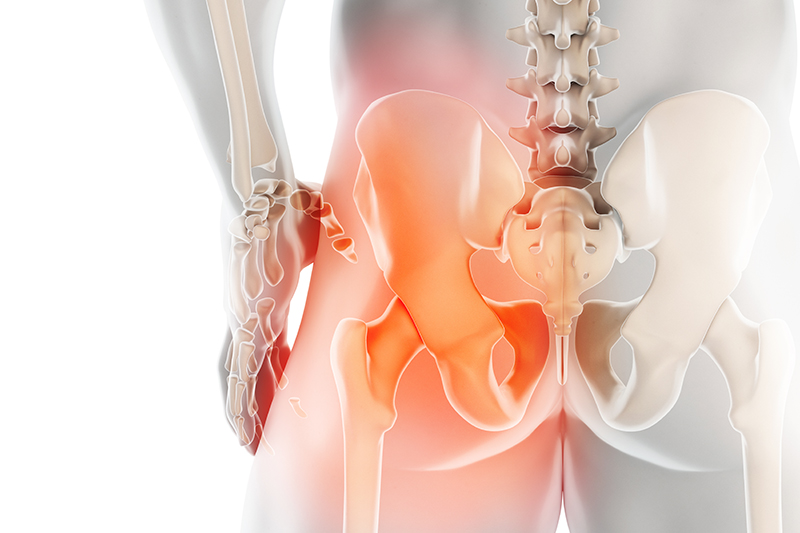

고관절이란

고관절은 흔히 엉덩이 관절이라고 불리며, 골반 쪽에 위치한 공-소켓(ball-and-socket) 형태의 관절입니다. 둥근 모양의 대퇴골두가 오목한 비구(acetabulum)에 맞물려 있어 골반과 허벅지를 연결하는 역할을 합니다.

이 관절은 체중을 지탱하고 보행, 달리기 같은 다리의 움직임을 가능하게 하는 핵심 구조입니다.